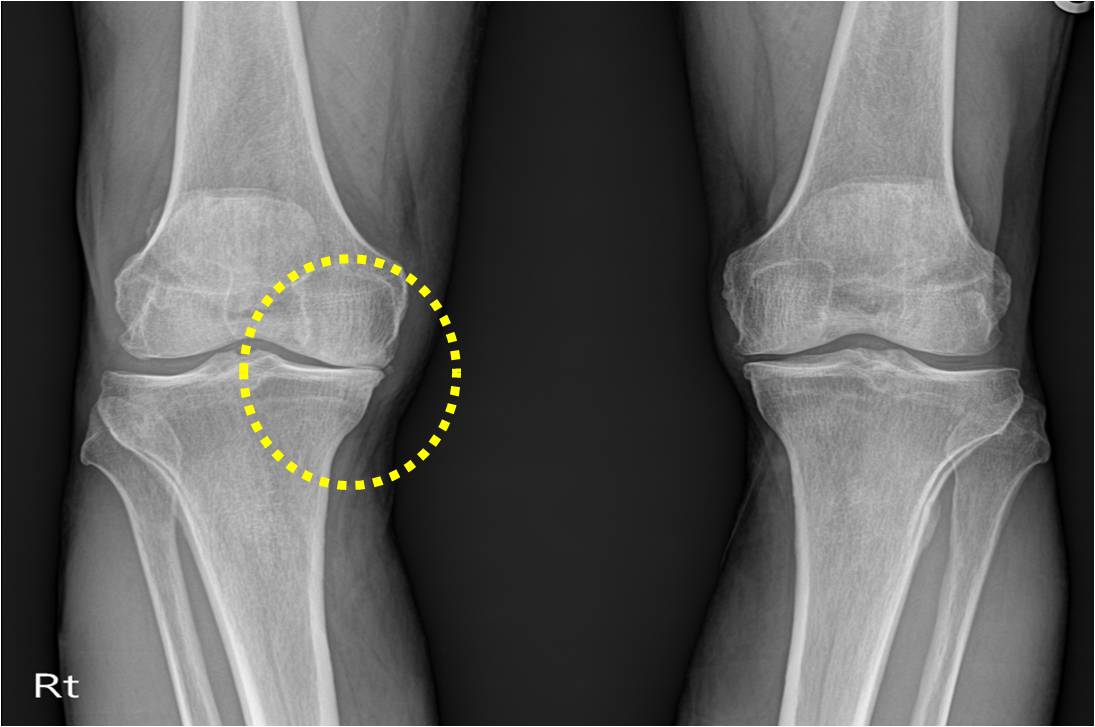

근육의 위축과 관절의 구축은 관절의 기형을 유발하게 되며, 관절의 연골이 닳아서 관절에 소리가 날 수 있습니다. 또한 관절의 열이 나거나 발적이 나타날 수 있고 관절이 변형되어 굽은 다리로 진행될 수 있습니다.

관절은 초기에 빨리 발견하기가 어렵다고 하는데 그 이유는 연골은 신경세포가 없기 때문에 손상을 입어도 자각하기가 쉽지 않기 때문입니다.

-똑바로 서 있을 때 무릎 사이에 주먹 하나가 들어갈 정도로 벌어진다